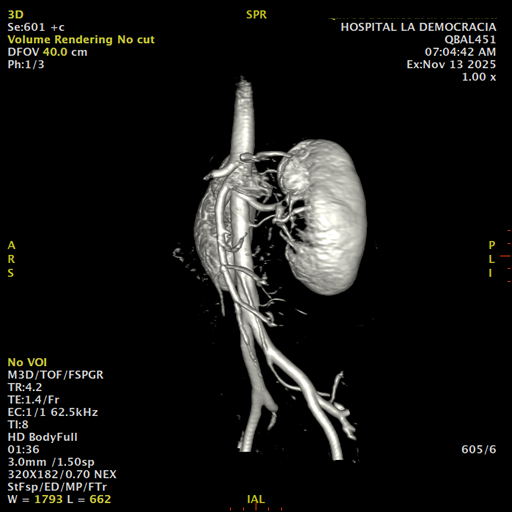

Paciente de sexo femenino, de 45 años de edad, refiere infecciones urinarias a repetición, no hay dolor, no refiere trauma, consulta por ardor al orinar, medico tratante le solicita resonancia abdominal, con énfasis en riñones, además un estudio de angiorenal.

Se prepara a paciente para ingreso a zona 4 del área de resonancia. Se coloca a paciente en decúbito supino, se canaliza en vena antecubital, se utiliza bobina de abdomen de 16 canales, se adquieren localizadores en tres planos, luego se procede a adquirir imágenes en diferentes planos, con secuencias echo spin y eco de gradiente, potenciadas a T1 y a T2.

Los sistemas colectores del riñón derecho y del riñón izquierdo, muestran alteración de sus calices primarios y secundarios, mostrando dilatación, la pelvis renal y el uréter se observan de características normales lo que indica que no hay proceso obstructivo.

Se observa dilatación del sistema calicial sin proceso obstructivo compatible con una anormalidad del desarrollo de los sistemas colectores de ambos riñones, definiéndose como una “megacaliosis”